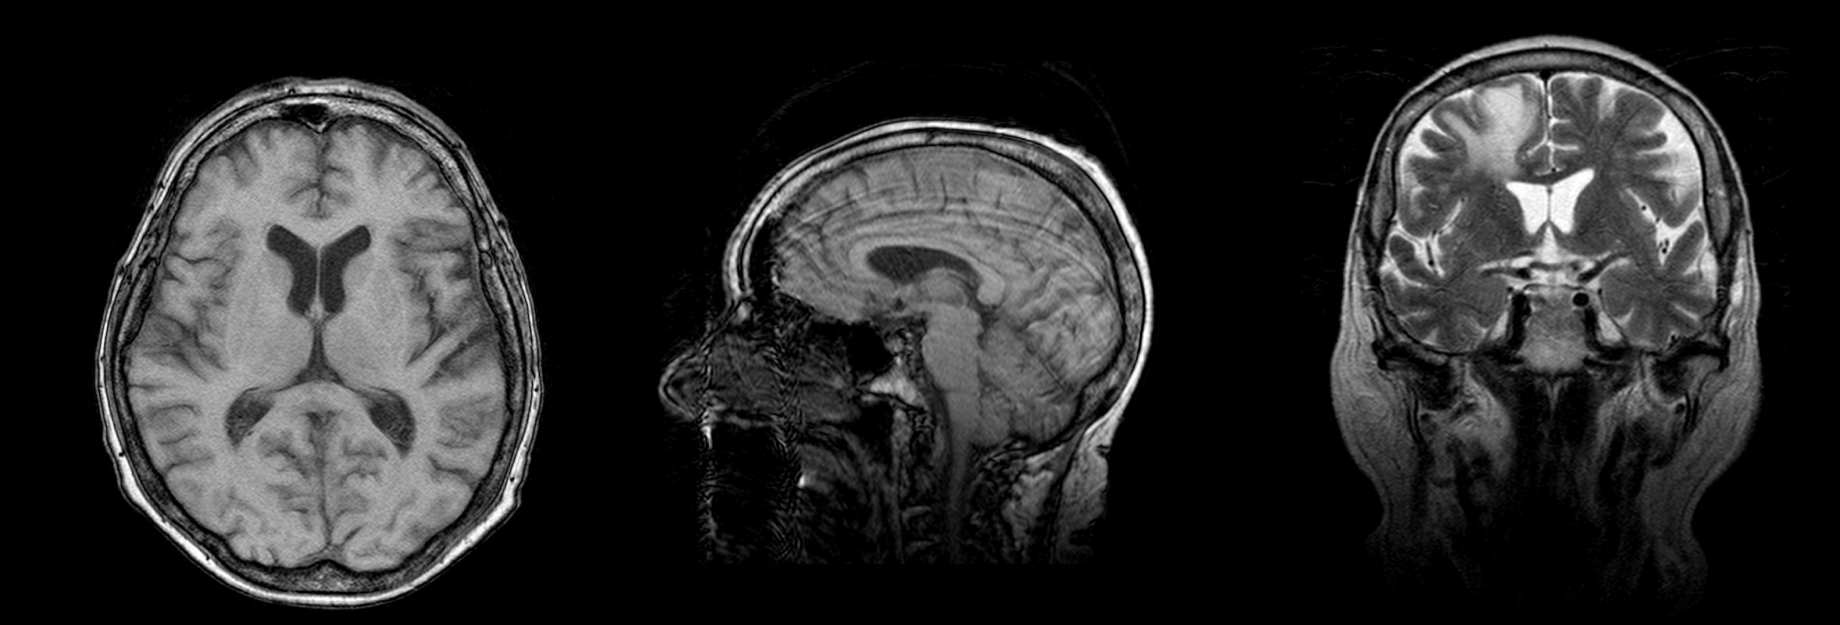

Brain Cancer MRI Object Detection & Segmentation Dataset

The dataset consists of .dcm files containing MRI scans of the brain of the person with a cancer. The images are labeled by the doctors and accompanied by report in PDF-format.

The dataset includes 10 studies, made from the different angles which provide a comprehensive understanding of a brain tumor structure.

MRI study angles in the dataset

The MRI scans provide high-resolution images of the anatomical structures, allowing medical professionals to visualize the tumor, its location, size, and surrounding tissues.